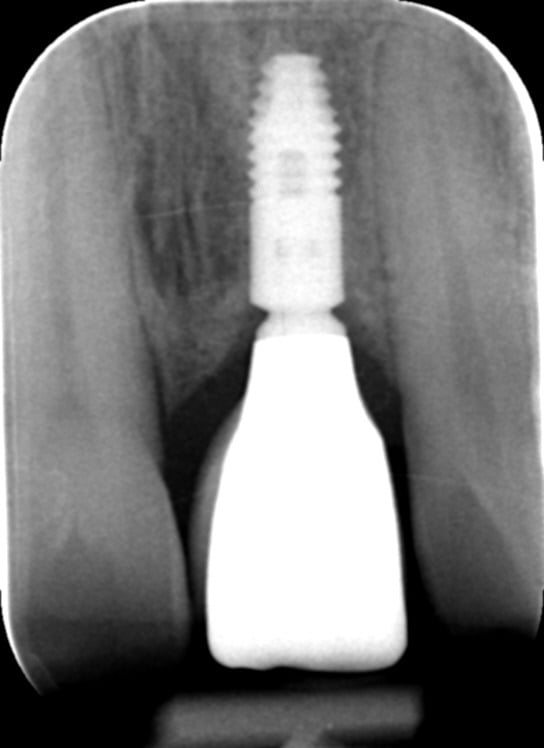

The fixture (titanium screw) replaces the function of a natural tooth root. Your jawbone attaches to the titanium threads of the fixture, providing a completely stable foundation for the new crown – a process known as osseo-integration. It usually takes twelve weeks for the bone to securely bond to the entire fixture surface.

A dental implant is simply a metal screw that is placed into the jawbone. It acts as an anchor for a false tooth or a set of false teeth. It functions very much like the root and crown of your natural teeth.

Your natural teeth are stable biting and chewing surfaces because your jawbone supports them. This is also true of dental implants. Successful dental implants become firmly embedded in the jaw through osseointegration, a natural process where the bone grows onto the implant surface.